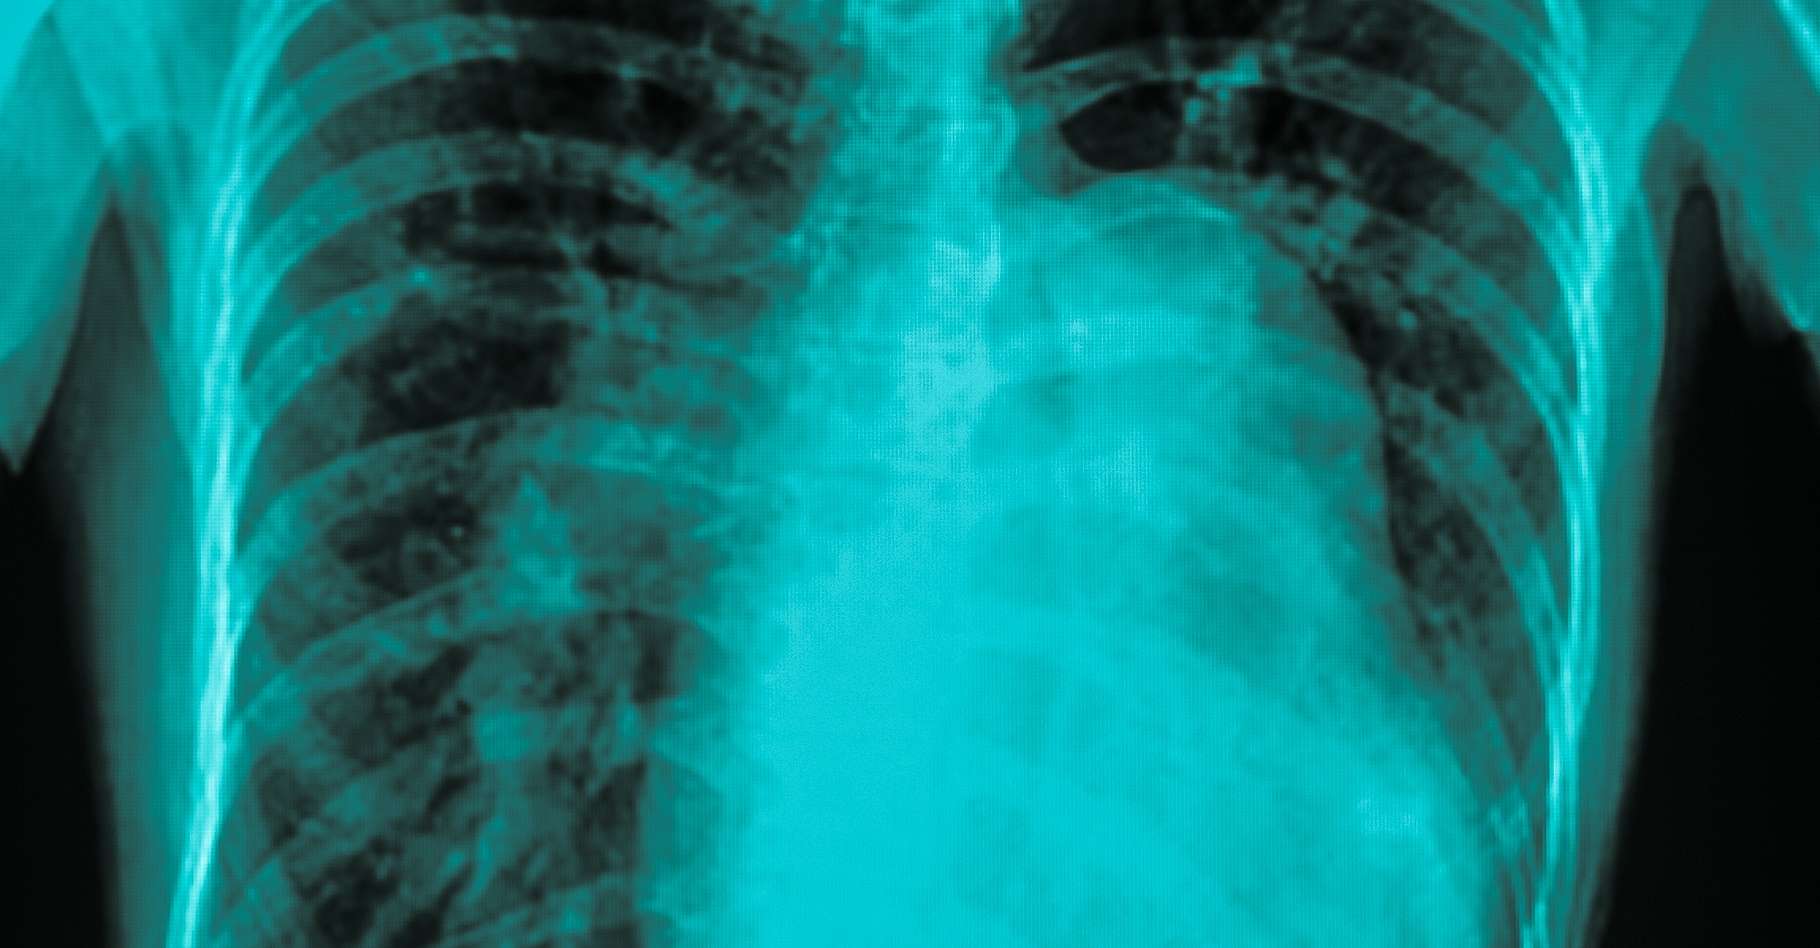

L'échographie cardiaque, réalisée sur échographe de type Philips EPIC, met en évidence une maladie de Barlow avec excès tissulaire sur les deux feuillets associé à un prolapsus des deux feuillets et un franc recul de l'anneau postérieur en systole.